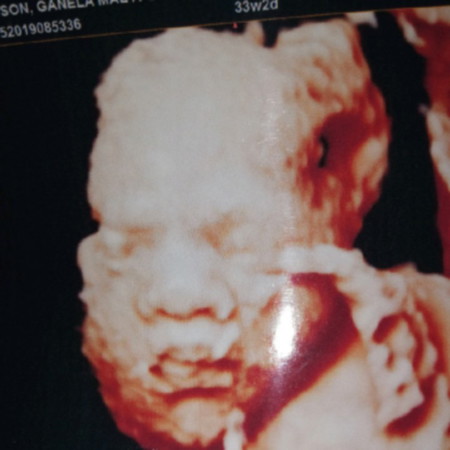

Babylove ❣️

hi po ilan months po nung nagpa 3D kayo?

Hi baby. ❤ Magkano po 3D mommy?

1k lng po mommy ❤️🤗